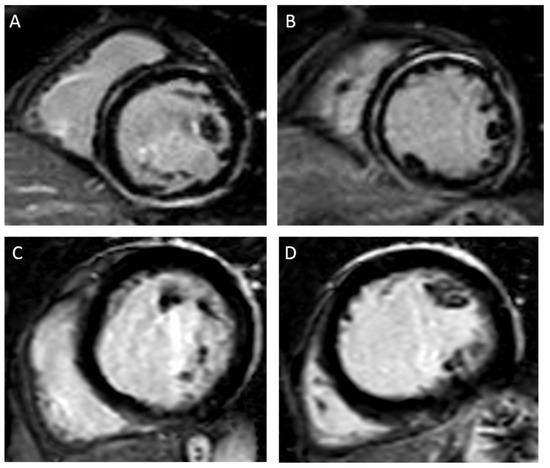

5. LGE and the Risk of Ventricular Arrhythmias and Sudden Cardiac Death

6. Extension of Late Gadolinium Enhancement and Association with Ventricular Arrhythmias

7. Location/Pattern of Late Gadolinium Enhancement and Association with Ventricular Arrhythmias

8. Insertion Points

9. Limitations of Late Gadolinium Enhancement